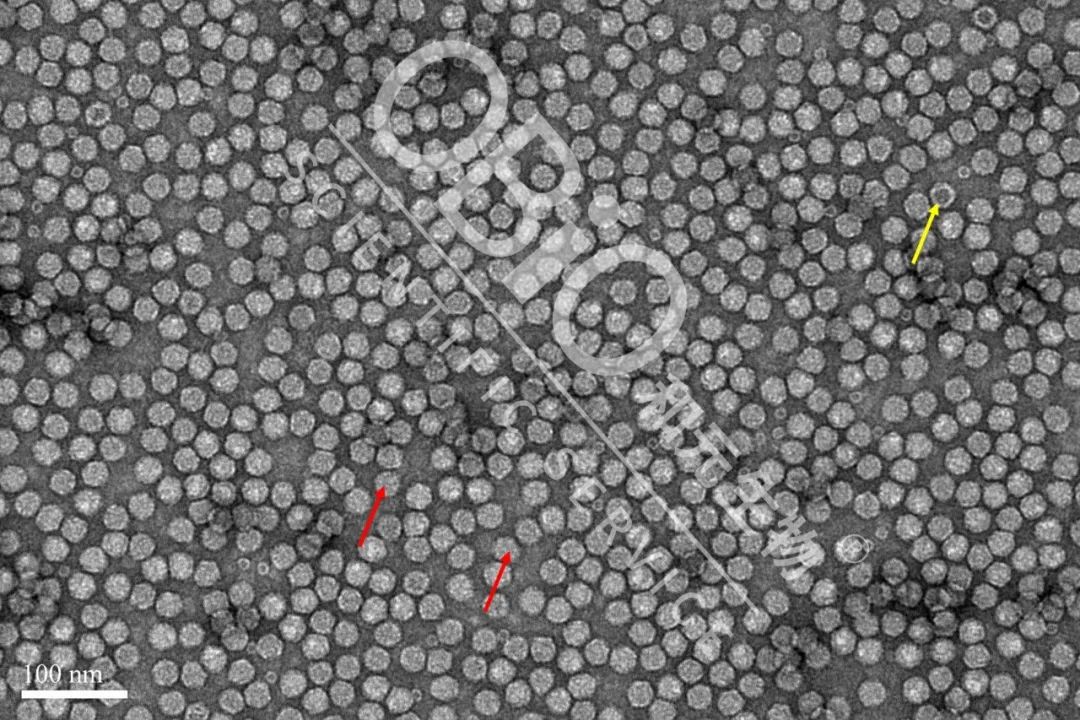

电镜毕竟:内包装DNA人类基因组的蠕虫新冠病毒粉末为安全板粉末(朱红色下箭头标志);空蠕虫新冠病毒粉末在期间普遍存在断层或空洞(金色下箭头标志)